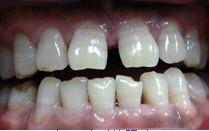

牙齒反合牙齒反合是對牙齒的上下不齊的一種稱謂。通俗的方式講,就是牙齒不齊,也就是平時常說的“地包天”。也被人們稱為"兜齒“,通常表現為下牙包住上牙,不但對咀嚼功能有影響,而且也會因為下巴突出而影響口型的整體美觀。

牙齒反合主要發生在乳牙期或恆牙期,有個別牙反合,也有多數後牙反合。可發生在單側,也可發生在雙側。